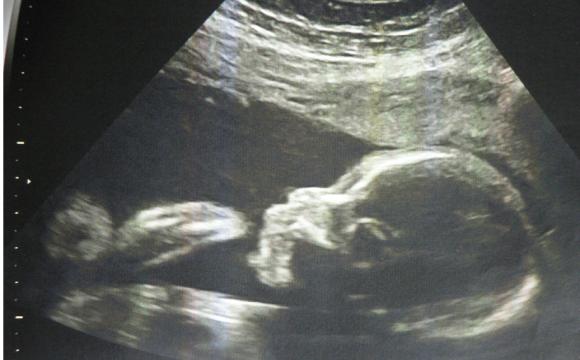

本周胎儿大约重450克,从头到臀长20厘米左右。这时期,胎儿的皮肤薄薄的,红红的,还皱巴巴的,样子像个小老头,但身体比例已经较为匀称。胎儿的嘴唇、眉毛和眼睫毛已清晰可见。宝宝的眼睛已经发育,视网膜也已形成,具备了微弱的视觉。宝宝的嘴唇越来越清晰,在胎儿的牙龈下面,幼小的牙蕾也开始发育了,显露出长牙的最初迹象。

怀孕第24周